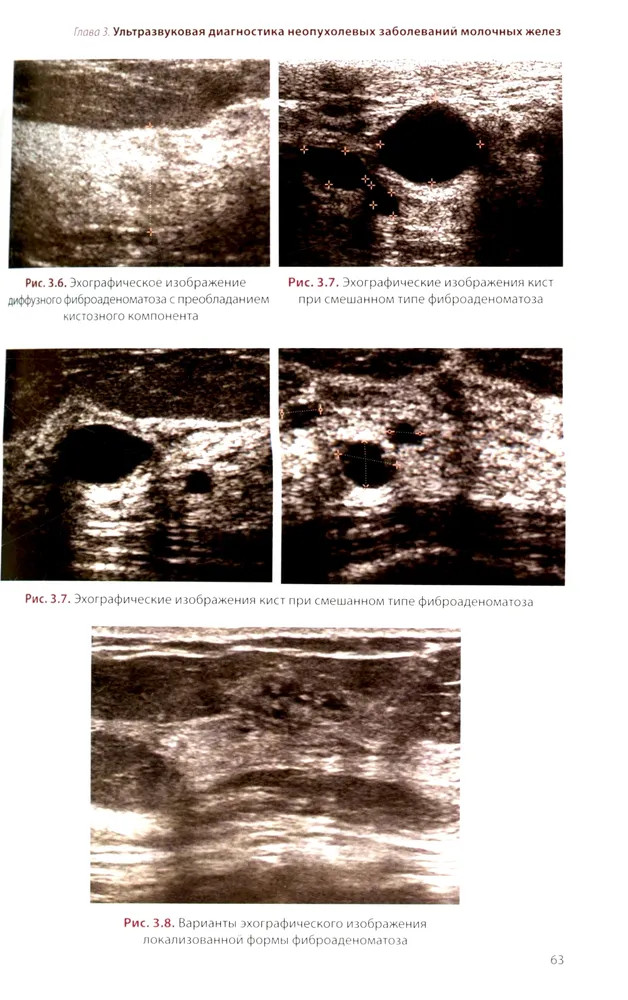

💳 Оплатить за товар можно при получении 🇰🇿 Есть бесплатная доставка по Казахстану от 1 дня 🎁 Копите бонусы с каждой покупки Руководство посвящено изучению возможностей различных методик УЗИ в диагностике доброкачественных и злокачественных опухолей молочных желез, доброкачественных процессов и воспалительных заболеваний. На основе анализа литературных данных рассматриваются вопросы этиологии, морфологии и классификации опухолей молочных желез. Отдельная глава посвящена методике и нормальной ультразвуковой анатомии молочных желез. Подробно изложены семиотика опухолей молочных желез, а также вопросы применения УЗИ в определении стадии опухолевого процесса согласно классификации TNM. Для специалистов по лучевой диагностике, а также врачей других специальностей в области маммологии. Руководство может быть рекомендовано для подготовки в системе последипломного непрерывного профессионального образования. |